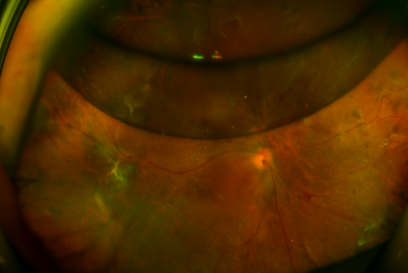

术前前节照相,显示晶体混浊,玻璃体血性浑浊